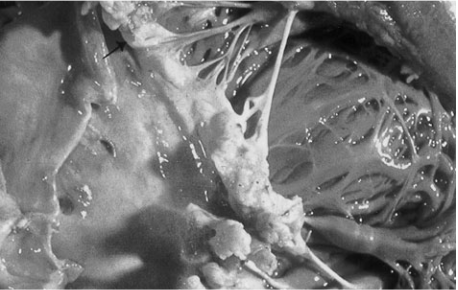

18.

A 69-year-old man with rheumatic heart dis-

ease presents to the emergency department

complaining of a fever and weakness on his left

side. On physical examination the patient is

weak in his left upper extremity and he draws

only the right half of a clock. Shortly after his

presentation, the patient dies, and an autopsy

is performed. A gross view of the patient’s heart

is shown in the image. Which of the following

is a risk factor for the type of lesion pictured?

The photograph de-

picts a vegetative growth on a native mitral

valve. Mitral valve prolapse (MVP), particu-

larly as a complication of rheumatic heart dis-

ease, is a risk factor for native valve infective

endocarditis. This is because altered blood flow

around a damaged valve provides the opportu-

nity for a clot to develop and harbor bacteria,

which gain access to the blood through a

wound, dental work, surgery, or intravenous

drug use. It can be prevented by replacing the

valve with a prosthetic valve.